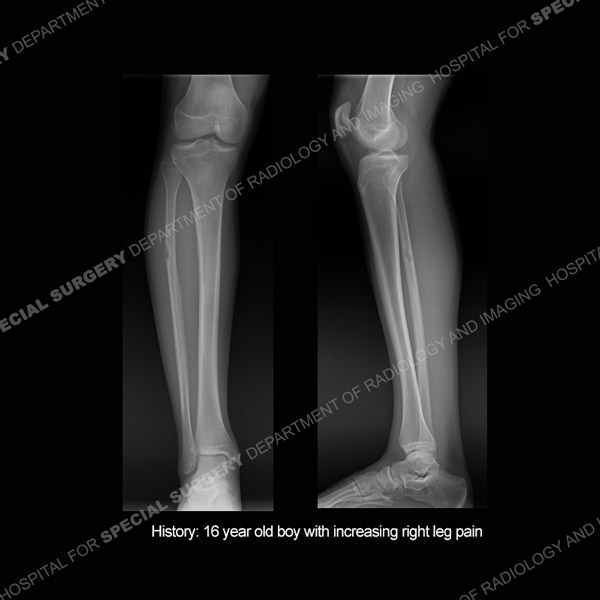

Featured Case of the MonthCase 216: 29-year-old woman with persistent left knee pain.